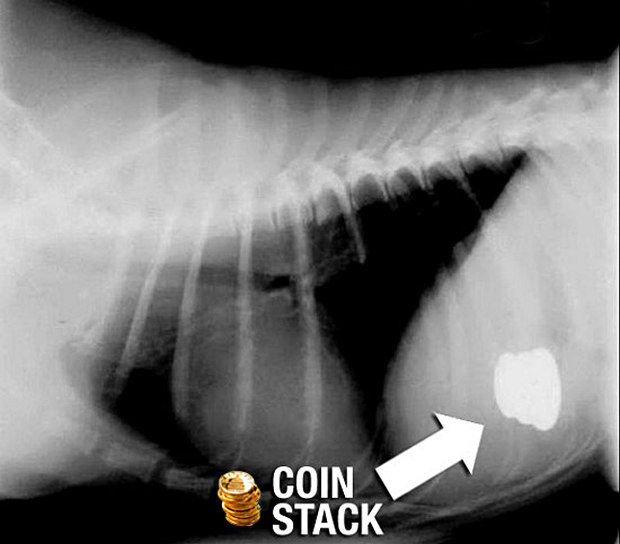

coin-xray-things-dogs-eat

coin-stack-xray-things-dogs-eat